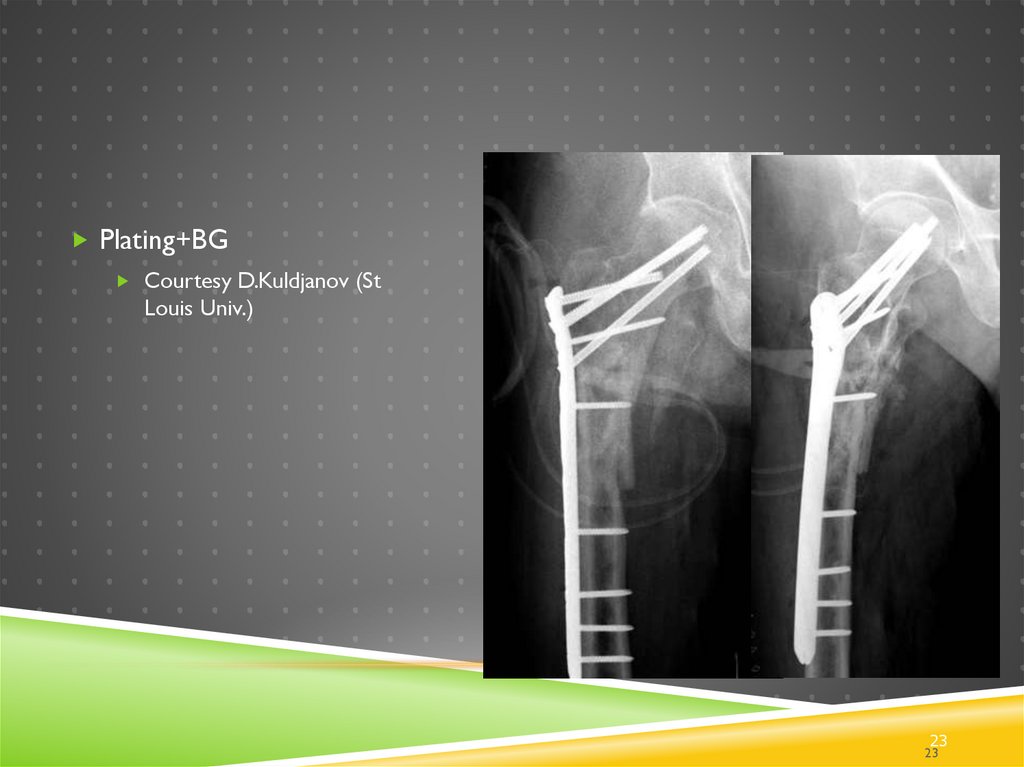

23.

Plating+BG

Courtesy D.Kuldjanov (St

Louis Univ.)

23